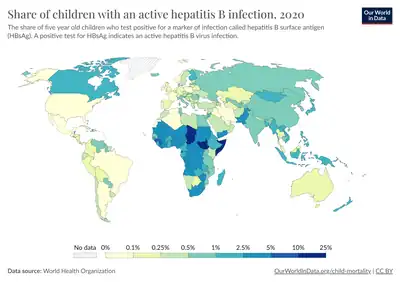

| Main uses | Chronic hepatitis B[2] |

Adefovir, sold under the brand name Hepsera, is a medicine used to treat chronic hepatitis B.[2] It may be used in those over the age of 11.[3] It may be effective in those resistant to lamivudine.[3] It is taken by mouth.[2]

It is used for treatment of hepatitis B.[7][8][9][10]